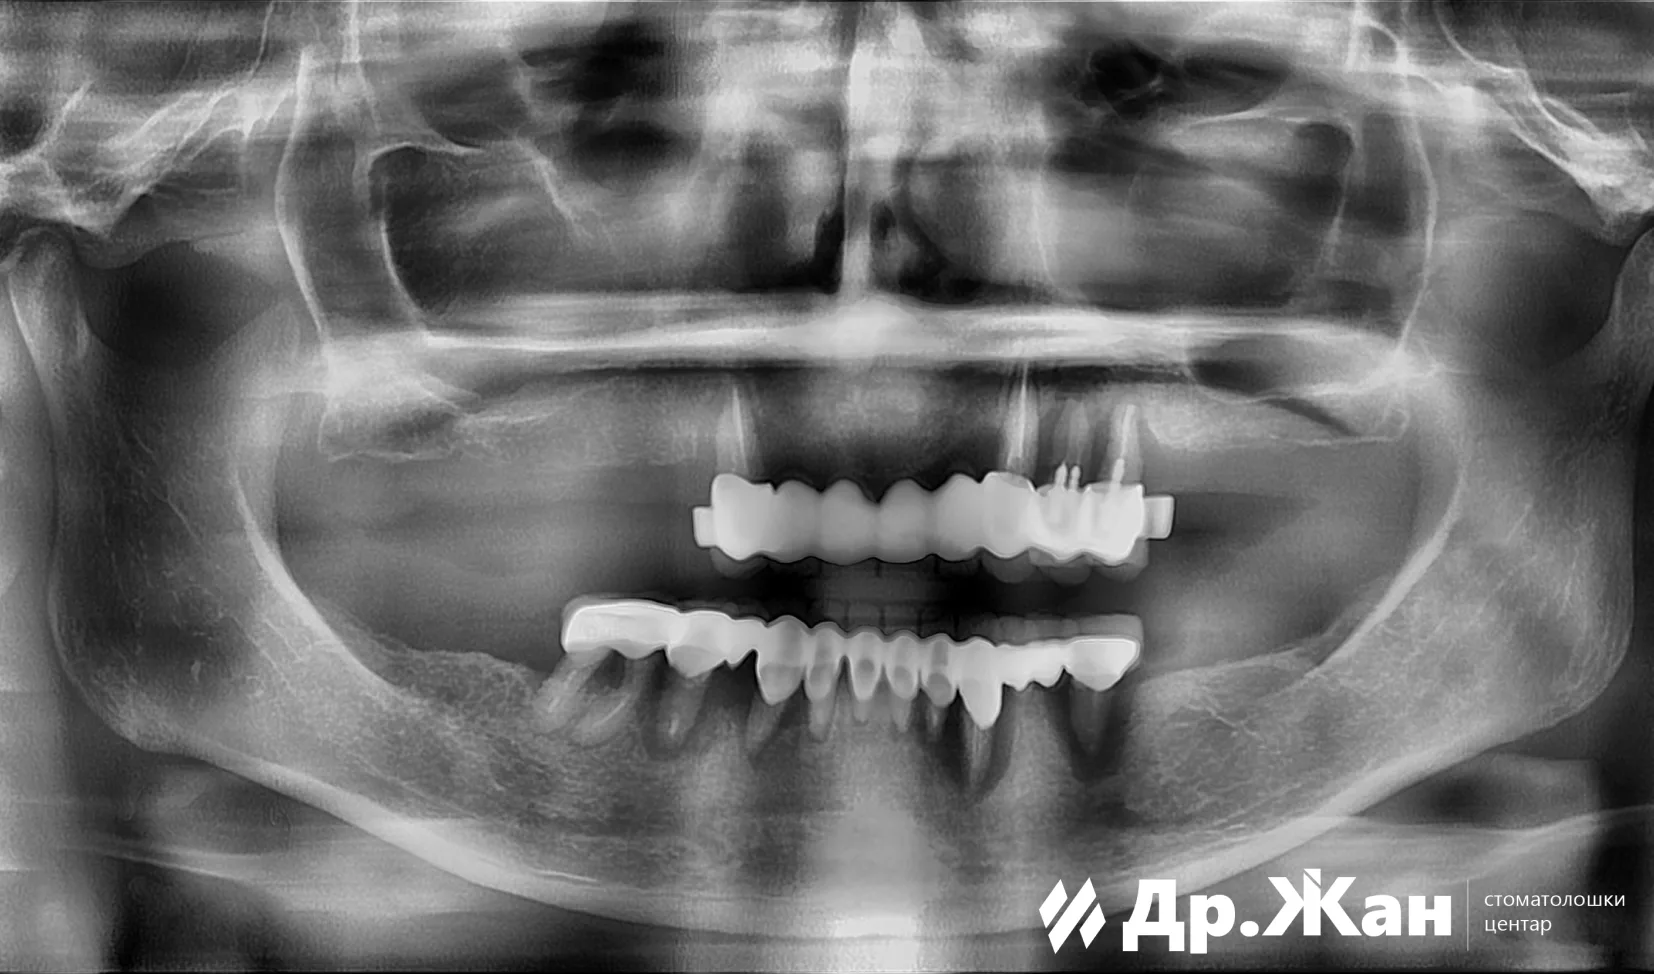

Оштетени мостови потпрени на забите

По прегледот и сите анализи, планот за терапија се состоеше од целосна реконструкција на устата со забни импланти. Сите заби беа отстранети, а имплантите беа поставени веднаш. На пациентката ѝ беа поставени привремени заби за време на периодот на заздравување.

ПРЕД